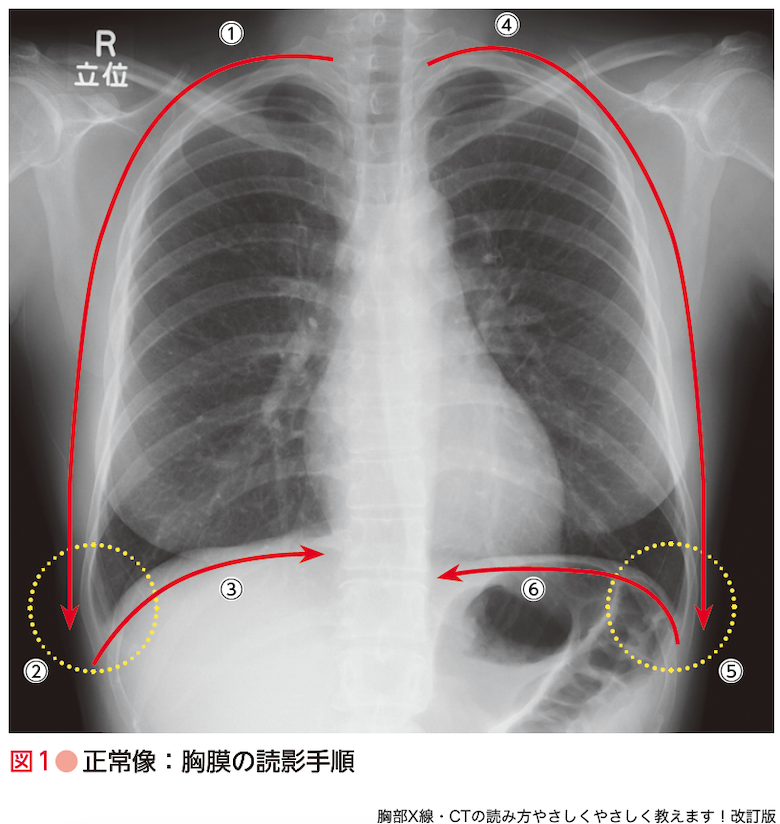

胸腺腫(きょうせんしゅ Thymoma) – 呼吸器疾患 - 神戸きしだ。Nerves of the Thorax: Atlas of Normal and Pathologic。胸腺腫(きょうせんしゅ Thymoma) – 呼吸器疾患 - 神戸きしだ。2024年度 新潟県魚沼産BLコシヒカリ10kg。Thoraco-abdominal CT scan. A shadow (90 mm in diameter) can。数ページ鉛筆による書き込みあり